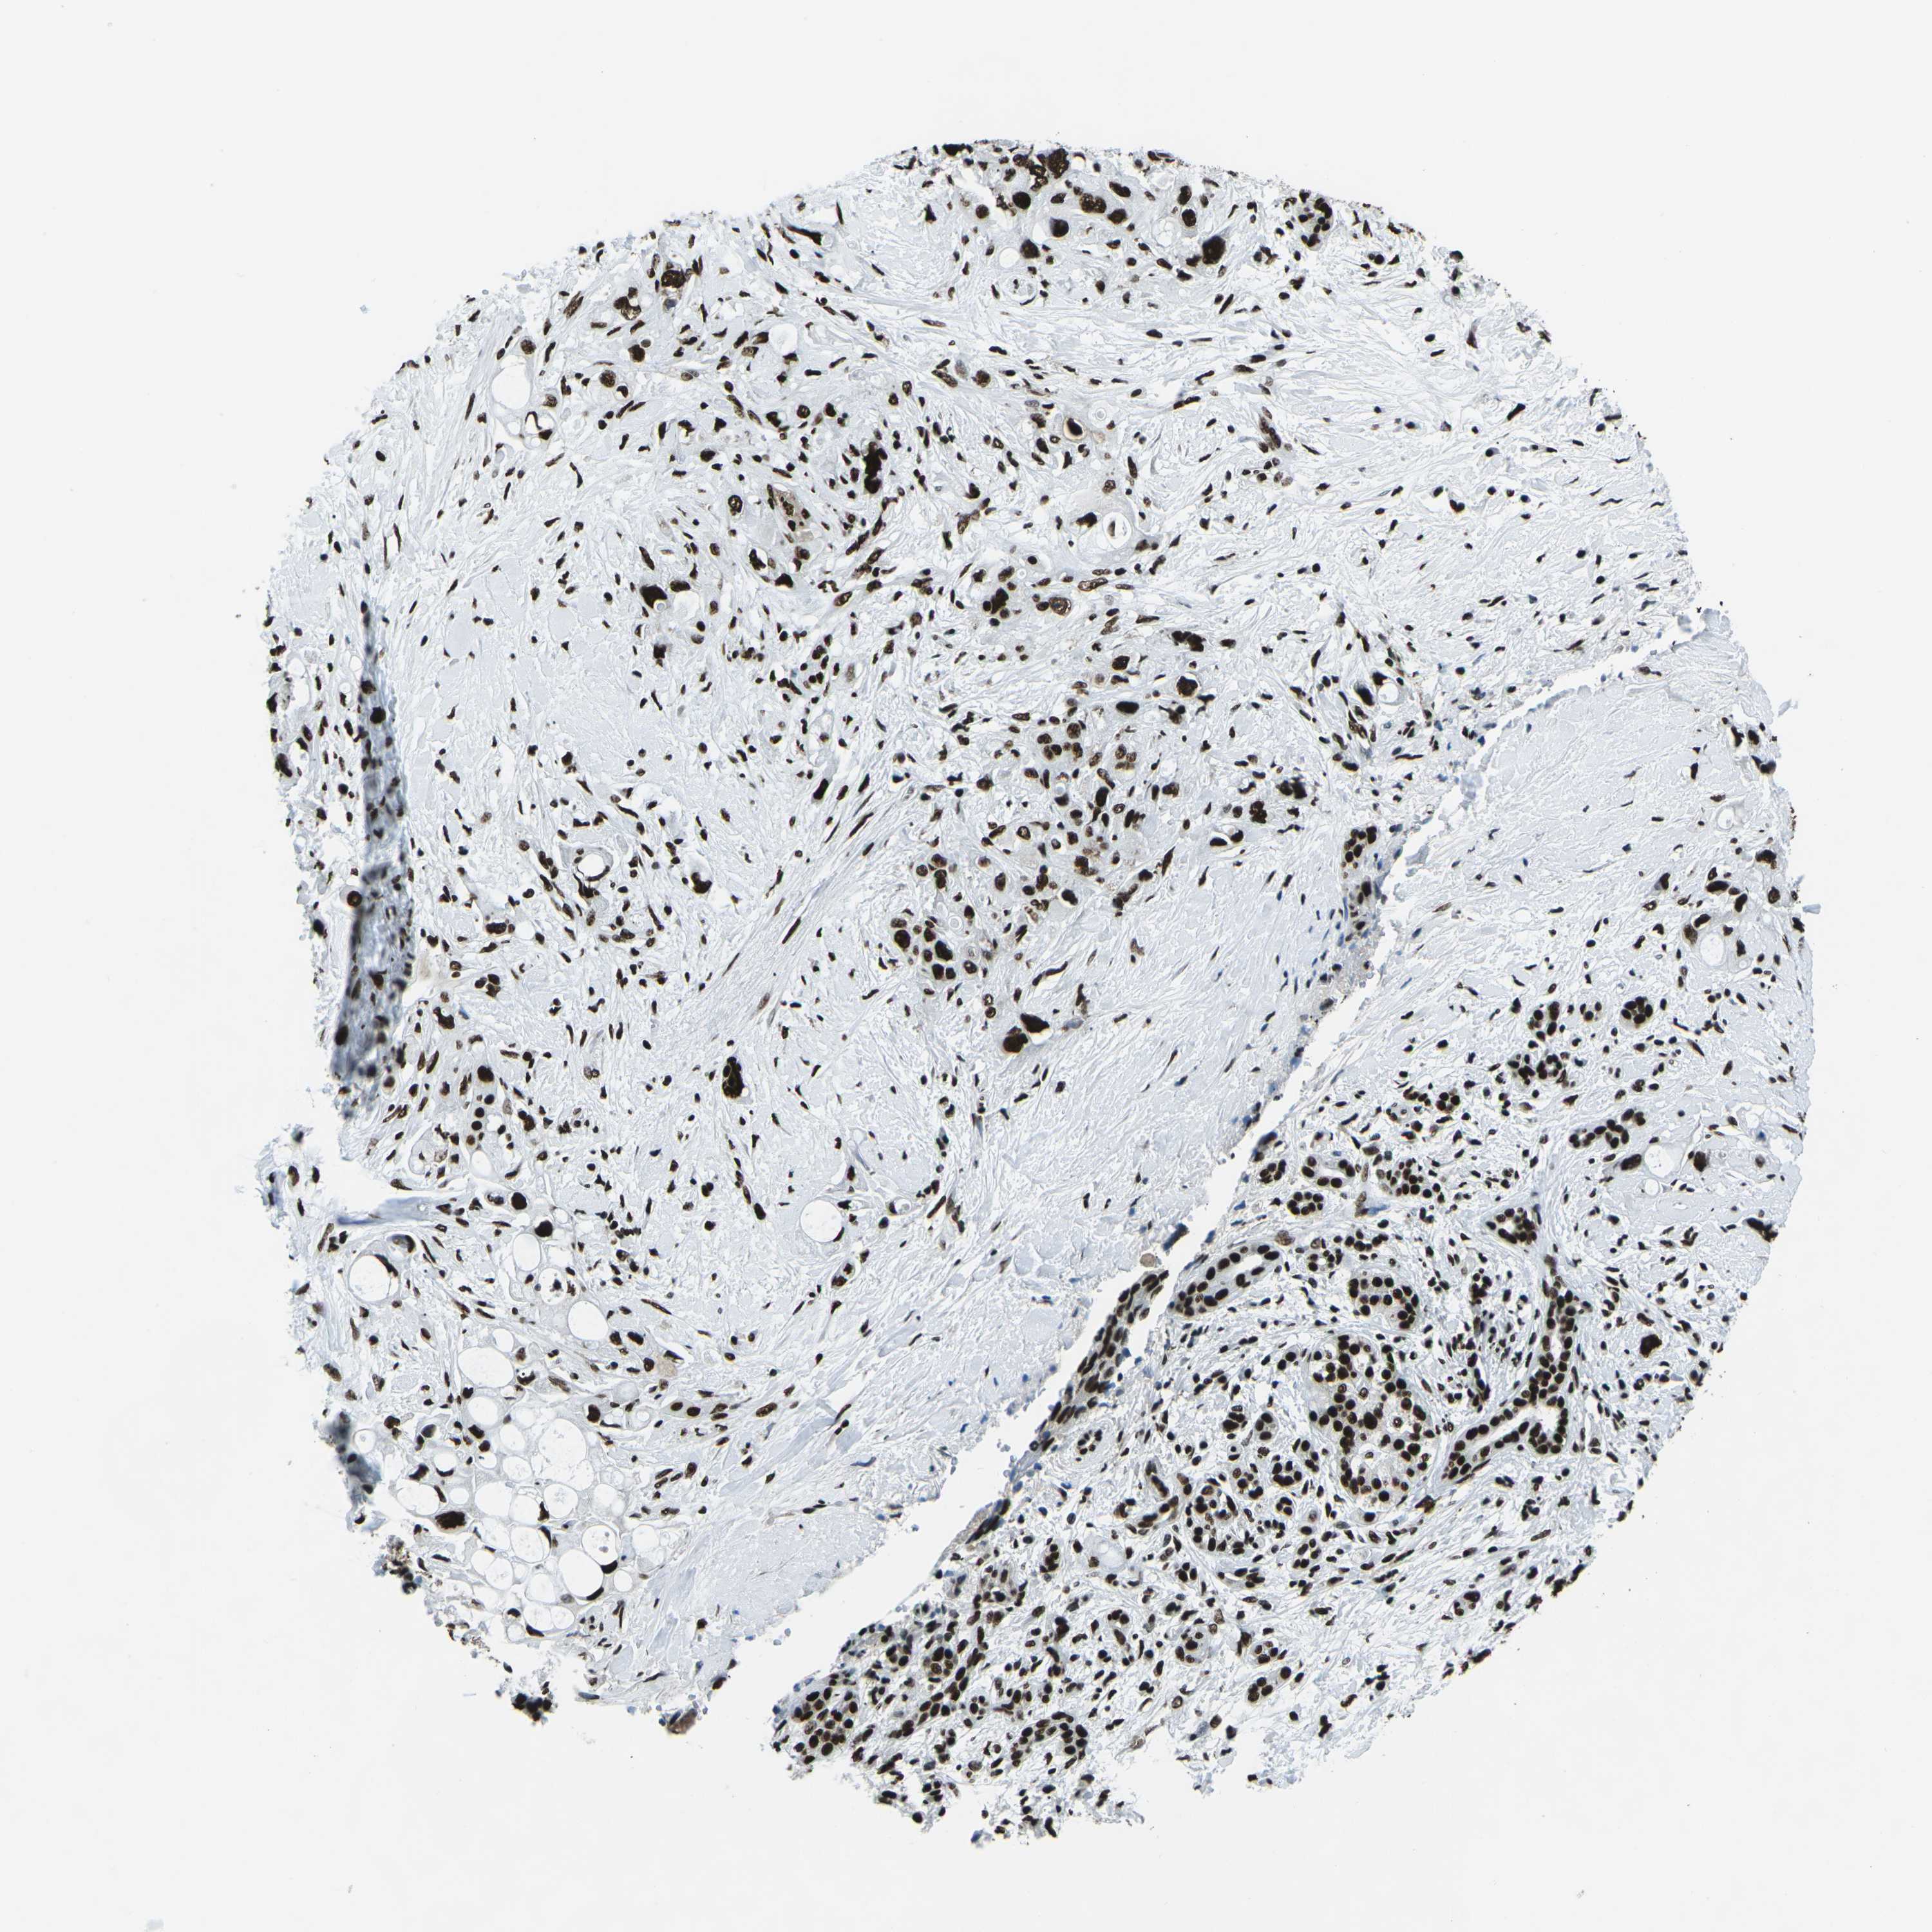

PANCREATIC CANCER - Protein expressioni

A mouse-over function shows sample information and annotation data. Click on an image to view it in a full screen mode. Samples can be filtered based on level of antibody staining by selecting one or several of the following categories: high, medium, low and not detected. The assay and annotation is described here.

Note that samples used for immunohistochemistry by the Human Protein Atlas do not correspond to samples in the TCGA dataset.

Antibody stainingi

Antibody staining in the annotated cell types in the current human tissue is reported as not detected, low, medium, or high, based on conventional immunohistochemistry profiling in selected tissues. This score is based on the combination of the staining intensity and fraction of stained cells.

Each image is clickable and will lead to virtual microscopy that enables deeper exploration of all samples and also displays staining intensity scores, fraction scores and subcellular localization as well as patient and tissue information for each sample.

Antibody HPA051748

Antibody HPA052661

Antibody CAB016326

Staining

High

Medium

Low

Not detected

Intensity

Strong

Moderate

Weak

Negative

Quantity

>75%

75%-25%

<25%

None

Location

Nuclear

Cytoplasmic/membranous

Cytoplasmic/membranous,nuclear

Adenocarcinoma, NOS